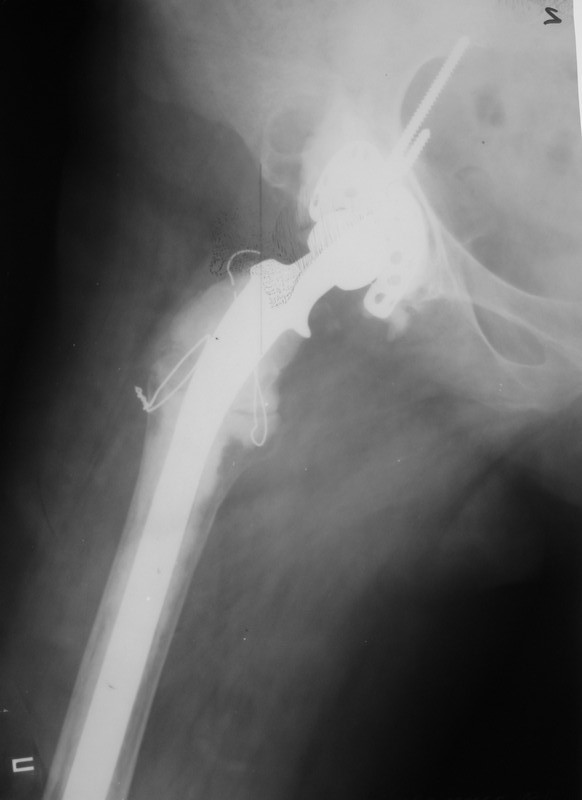

Уважаемые коллеги,в клинику поступила пациентка 51год с нестабильным антипротрузионным кольцом и вывихом эндопротеза. В течени длительного времени у пациентки ревматойдный полиартрит с приемом преднизолона. В 1994 году произведено эндопротезирование правого тазобедренного сустава бесцементным эндопротезом Biotronic. В 2000году по поводу нестабильности эндопротеза проведено ревизионное вмешательство-удаление чашки и ножки, некрэктомия. Установка антипротрузионного кольца, цементной чашки и ревизионной цементной ножки Beznoska. В 2007году выявлена клиникорентгенологическая картина нестабильности кольца. В 2008году пациентка упала, произошел вывих эндопротеза и дислокация кольца с переломом винтов. Планируем ревизионное вмешательство-удаление кольца, чашки, винтов, пластика верхнего края вертлужной впадины массивным аллотрансплантатом с последующей установкой антипротрузионного кольца типа Burch-Shneider. Прошу коллег занимающихся ревизионным эндопротезированием высказать свое мнение.PS:у больной в 1998 году установлен цементный эндопротез Beznoska левого тазобедренного сустава и в 2003 году установлен цементный эндопротез De Puy LCS правого коленного сустава.

Ситуация непростая, во время операции может оказаться дефект не только передне-верхнего отдела ВВ, но и слабость задней стенки. В этом случае результаты установки кольца Б-Ш могут быть не столь оптимистичны. Использование массивного аллографта опасно развитием позднего остеолиза и как следствие - нестабильности конструкции, плюс к этому-реальная опасность инфекционного осложнения. В последнее время (и мы будем говорить об этом на Вреденовских чтениях - маленькая рекламка:)) мне все больше импонирует ТМТ, это трабекулярный металл с очень высокой пористостью. Если рим ВВ позволяет хоть немного зацепиться полусферической чашкой, то успех гарантирован. При наличии сегментарного дефекта лучше в этой ситуации использовать трабекулярные аугменты и женить с ТМТ ревизионной чашкой при помощи цемента. Все небольшие дефекты мы заполяем костной стружкой (алло) в последнее время стали применять остеосет Т (с тобромицином). Если же совсем все плохо, то тогда палочкой-выручалочкой является кольцо Б-Ш., которое можно установить по ситуации, а анатомические углы выставить ПЭ вкладышем.